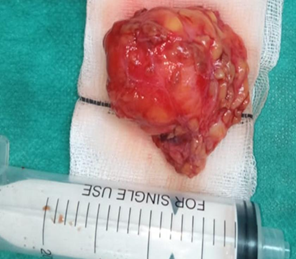

Under general

anesthesia, superficial parotidectomy with preservation of facial nerve was

performed. Surgery began with a modified Blair’s incision, the parotid gland

was then exposed. After identifying the facial nerve trunk and its

branches, the fatty mass was completely excised together with part of the

adjacent superficial lobe from which it was originating (Figure 3).

During

surgery, frozen section was sent to decide further course of action. Gross

examination of the specimen sent disclosed a mass of adipose tissue measuring

4,5x 3,3 x1,1 cm surrounded by salivary gland tissue. Thus, the frozen section

examination reported that the mass is likely a parotid lipoma, negative for

malignancy.

Figure 3. Intraoperative view after

superficial parotidectomy with preservation of the facial nerve.